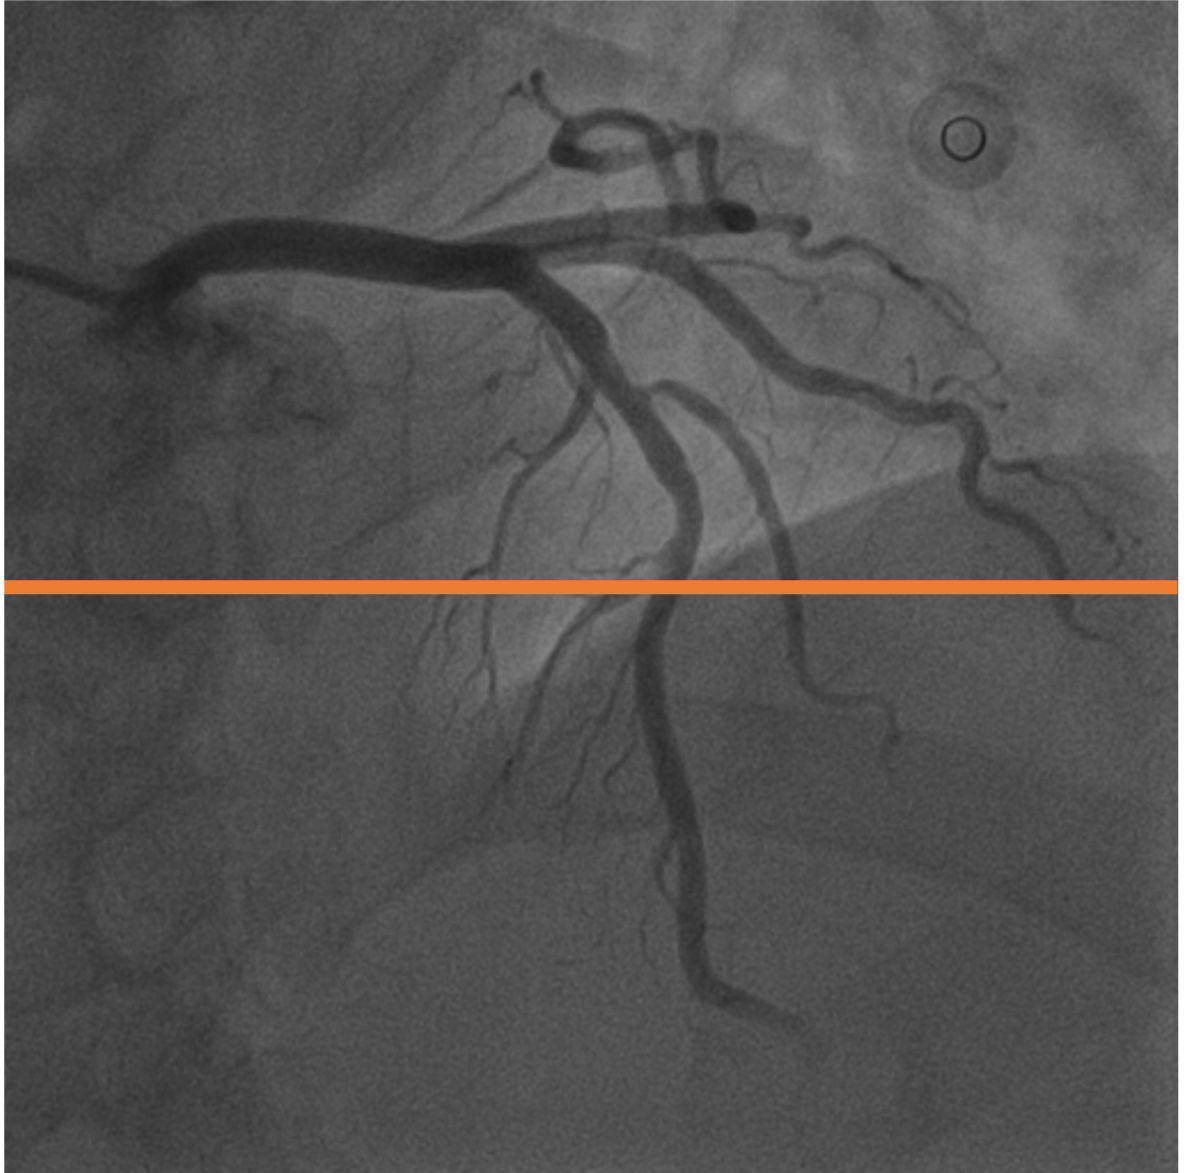

7 Temporal Coherency

Our method takes an entire X-ray video as input, thus producing segmentation results with better temporal coherency. Temporal coherency is essential for making medical diagnoses, especially when dealing with blood flow in vessels. Therefore, we conduct visual comparisons between our method and other compared methods by slicing horizontally or vertically and stacking the segmentation results. The results in Fig. 14 show our method strikes a better balance between segmentation accuracy and temporal coherency. While other baseline methods either produce false segmentation results or do not maintain consistent prediction along the temporal dimension.